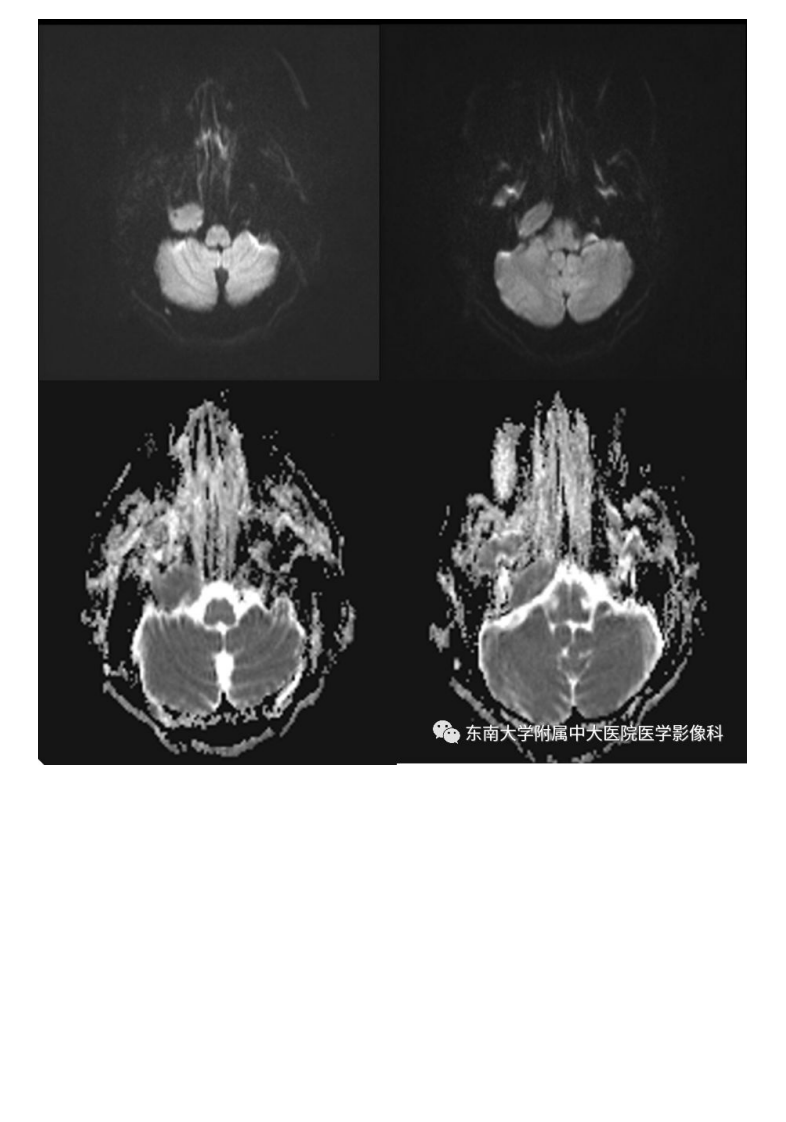

20190930_3【晨读结果公布】2019.09.29头颈部系统疾病.pdf